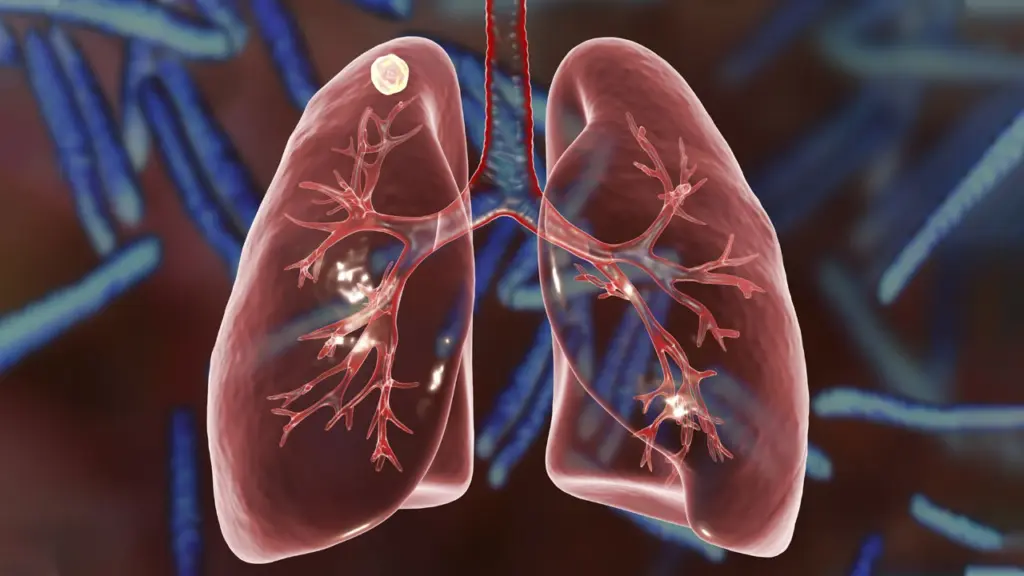

EVRE 1

EVRE 1

Tümör sadece akciğerdedir ve lenf bezlerine sıçramamıştır.

EVRE 2

EVRE 2

Tümör biraz büyümüş veya yakındaki lenf bezlerine yayılmıştır.

EVRE 3

EVRE 3

Tümör göğüs kafesi içindeki mediyasten lenf bezlerine yayılmıştır.

EVRE 4

EVRE 4

Kanser diğer organlara veya karşı akciğere sıçramıştır.

Akciğer nodülleri, gelişen radyolojik görüntüleme teknikleri sayesinde günümüzde tesadüfen çok daha sık tespit edilmektedir. Radyoloji raporlarında görülen “akciğer...

Akciğer nodülleri, gelişen radyolojik görüntüleme teknikleri sayesinde günümüzde tesadüfen çok daha sık tespit edilmektedir. Radyoloji raporlarında görülen “akciğer nodülü” ifadesi...